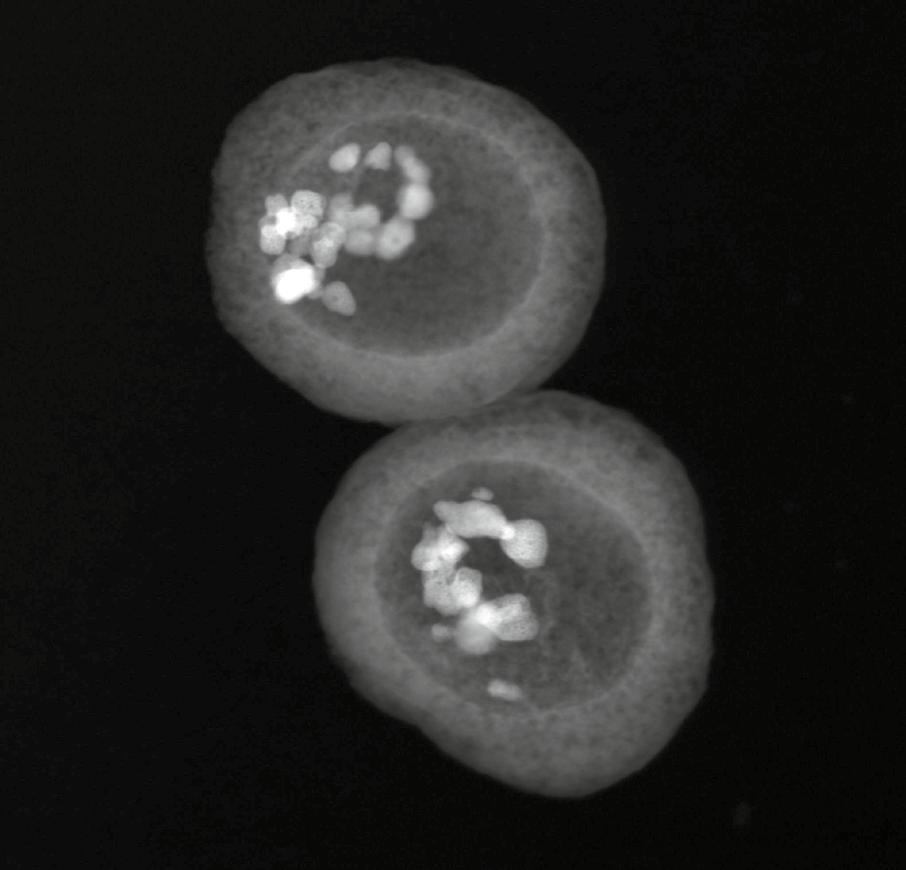

Scanning Transmission Electron Microscopy image with high-angle annular dark-field detector (HAADF-STEM) of hybrid PMO-inorganic thermometers developed in project NORTH. The inorganic inner cores generate the thermometry properties, whereas the cavities and porous nature of the PMO walls allows loading it with an anti-cancer drug.

A lot of thermometers are currently made using lanthanides, yet these are purely inorganic particles that can’t really be loaded with drugs or used to produce an effective photodynamic therapy (PDT) agent. This is where the PMOs come into play. “The PMO not only makes the hybrid material more biocompatible, but it also adds porosity. You can then load a PDT agent or an anti-cancer drug such as doxorubicin for example,” says Professor Kaczmarek. The project team is now looking to develop effective nanoparticles using these materials; Professor Kaczmarek says size and shape are important considerations. “Larger particles can be toxic, while we also don’t want the nanoparticles to be too small, as that causes some retention problems. Around 100 nanometres would be

The idea is that the particle would be activated with light once it reaches a specific location in the body, such as the site of a tumour for example. This would then allow researchers to monitor temperatures, and potentially release an anti-cancer drug. “We aim to use two wavelengths of light simultaneously, one of which could be used to activate the material to show a temperature read-out,” explains Professor Kaczmarek. A lot of progress has been made in this area over the course of the project, with Professor Kaczmarek and her colleagues demonstrating that their hybrid particles can combine thermometry and drug delivery. “We see that there’s some signal interference, which is related to the presence of spectral overlaps. But we also see that we can still use the nanoparticles as a thermometer and as a drug release agent simultaneously without any issues,” she continues.